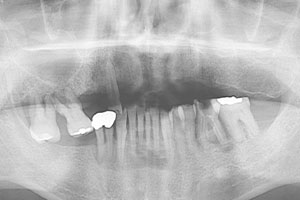

치료증례 전후사진

Before & After